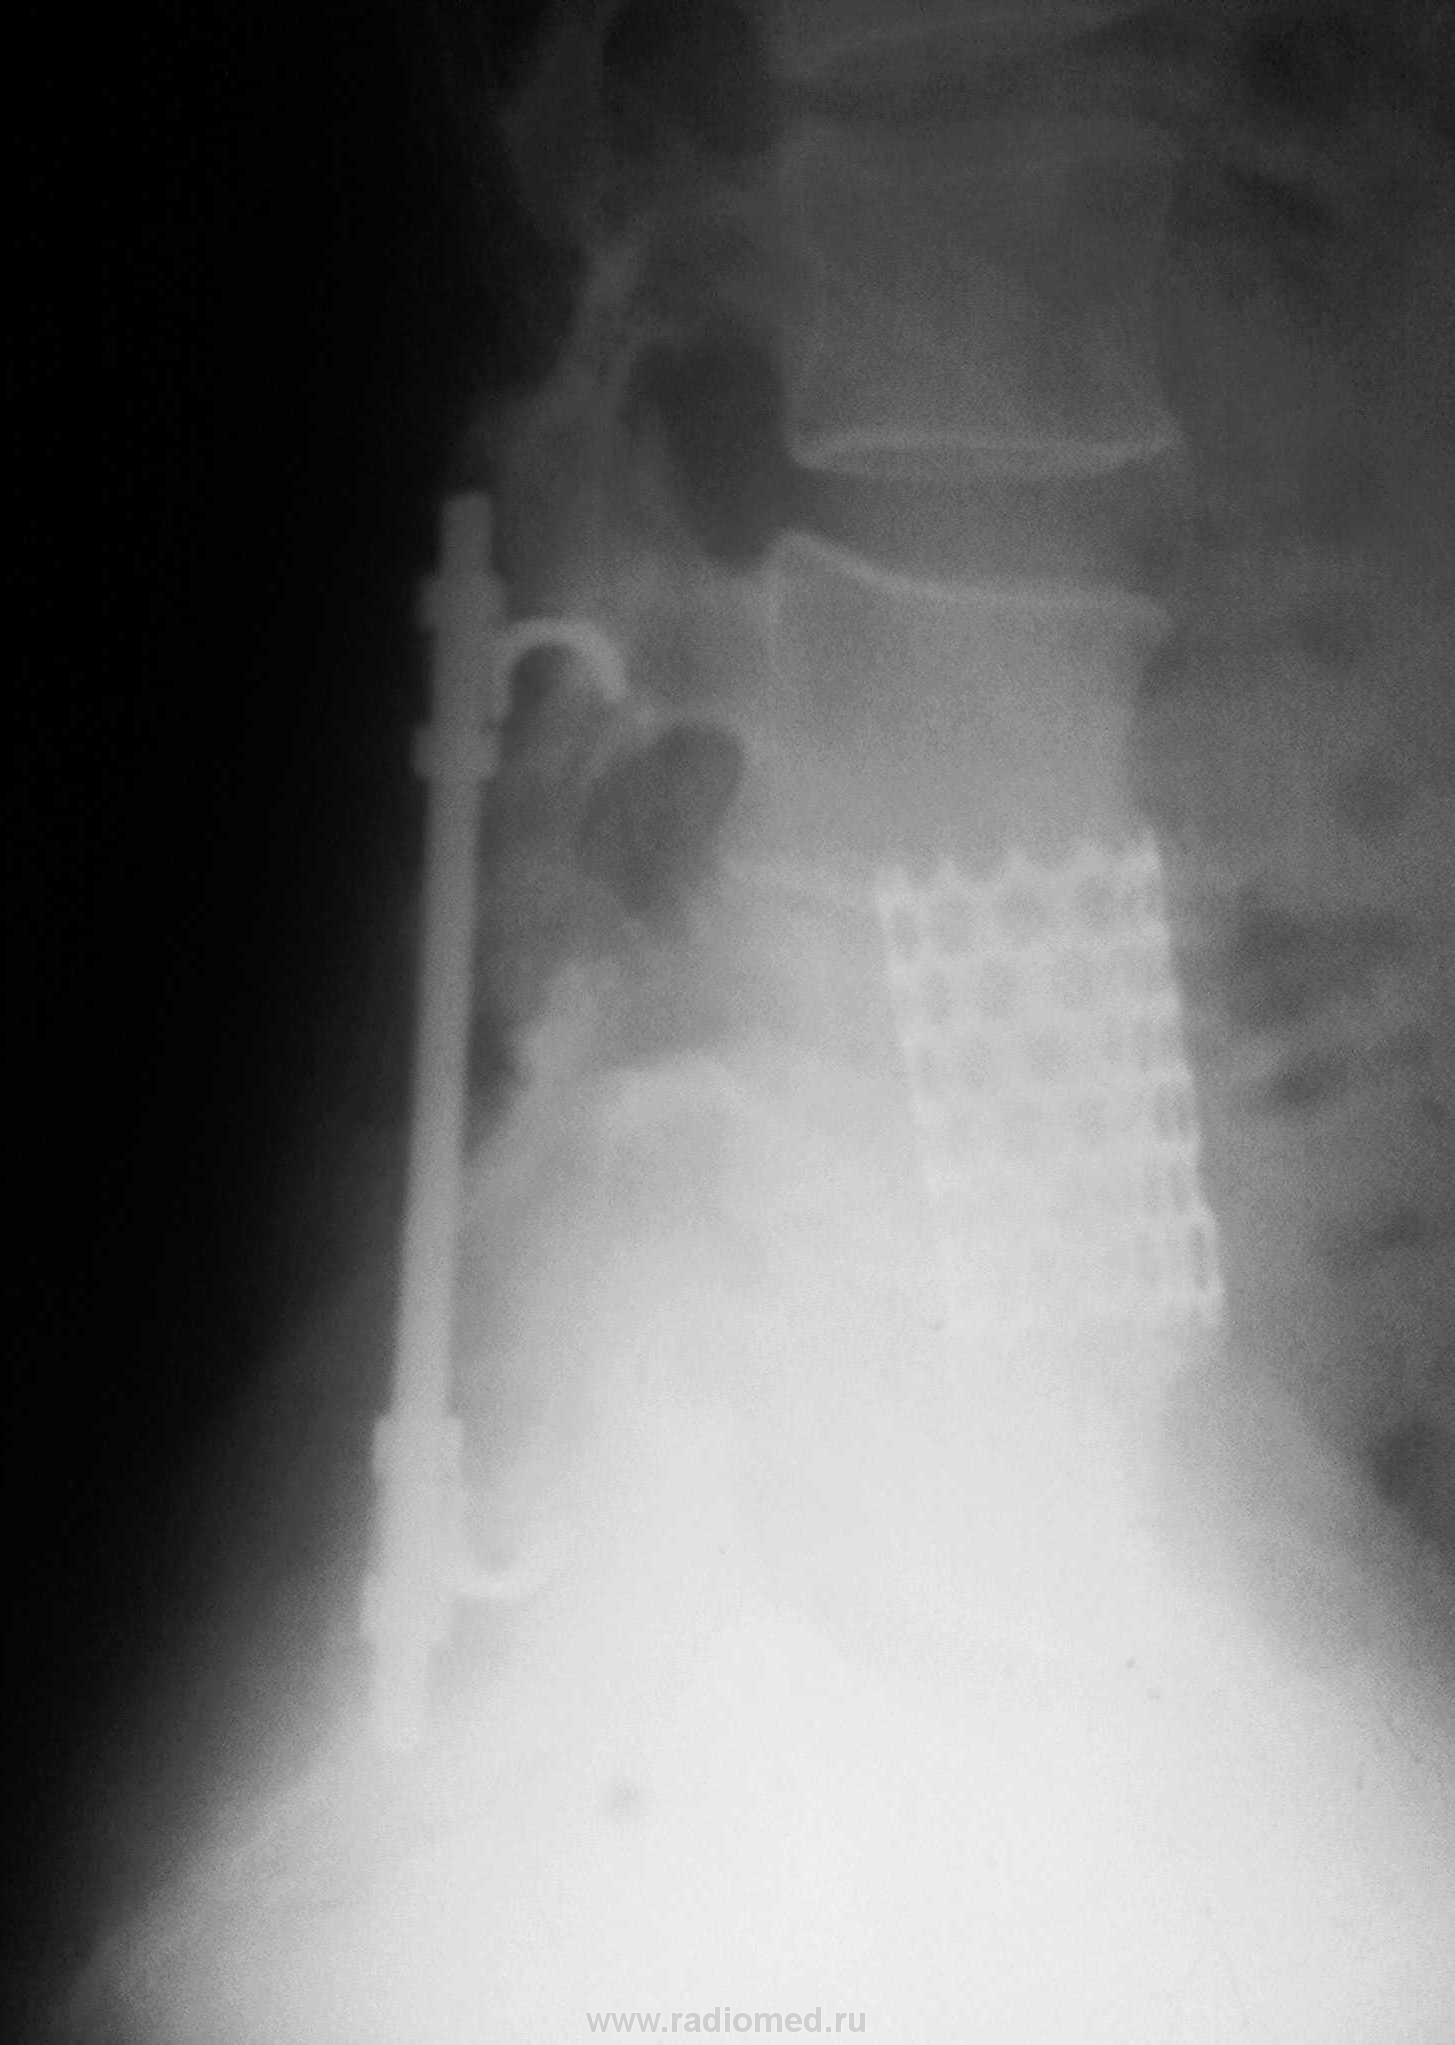

Установлен дистрактор за дужки LIII и Lv.

Это так называемые "педякулярные крючки", методика будет называться педикулярная фиксация тел позвонков, обычно проводят транспедякулярную фиксацию.

В Вашем случае можно так сказать сочетание методик, дело в том, что это скорее всего не просто трубка а титановая трубка-имплантант, при классическом спондилодезе идёт замещение диска в межпозвонковом сегменте на имплантант, в данном случае я так понимаю был компрессионно-оскольчатый перелом тела позвонка, часть его удалили тем самым заменив этим имплантантом, но для разгрузки на данный сегмент сделали ещё и педикулярную фиксацию.

Спондилодез так или иначе наступит - передний (для этого тело и заместили кейджем) и задний - обычно достигается использованием аутокости. Правда, чаще всего используют не крючки, а конструкцию с винтами в тело (ТПФ - транспедикулярную фиксацию). Стабильность получше.